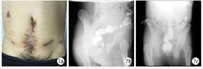

立位腹平片提示OTSC夹在位,并于2天后复查患者窦道造影提示原窦道已较OTSC治疗前明显减小,但仍可看到少量造影剂经内瘘口进入乙状结肠肠腔内,为促进肠瘘进一步愈合,遂经皮肤外瘘口注入纤维蛋白胶充填瘘管,封堵瘘口。加强外瘘口持续换药,并继续应用禁食、抑酸、肠外营养支持治疗2周后,复查腹部CT提示瘘口周围组织未见明显渗出(图6),逐步过渡为经鼻胃管肠内营养支持治疗,考虑患者病情稳定,予以办理出院,实行家庭肠内营养支持治疗。

出院后3个月随访,复查结肠造影提示全结肠未见造影剂外溢(图7),外瘘口愈合良好,考虑患者乙状结肠吻合口瘘愈合,逐步过渡为经口进食。